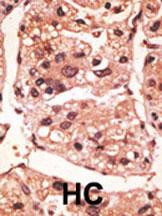

Formalin-fixed and paraffin-embedded human cancer tissue reacted with the primary antibody, which was peroxidase-conjugated to the secondary antibody, followed by DAB staining. This data demonstrates the use of this antibody for immunohistochemistry; clinical relevance has not been evaluated. BC = breast carcinoma; HC = hepatocarcinoma. |